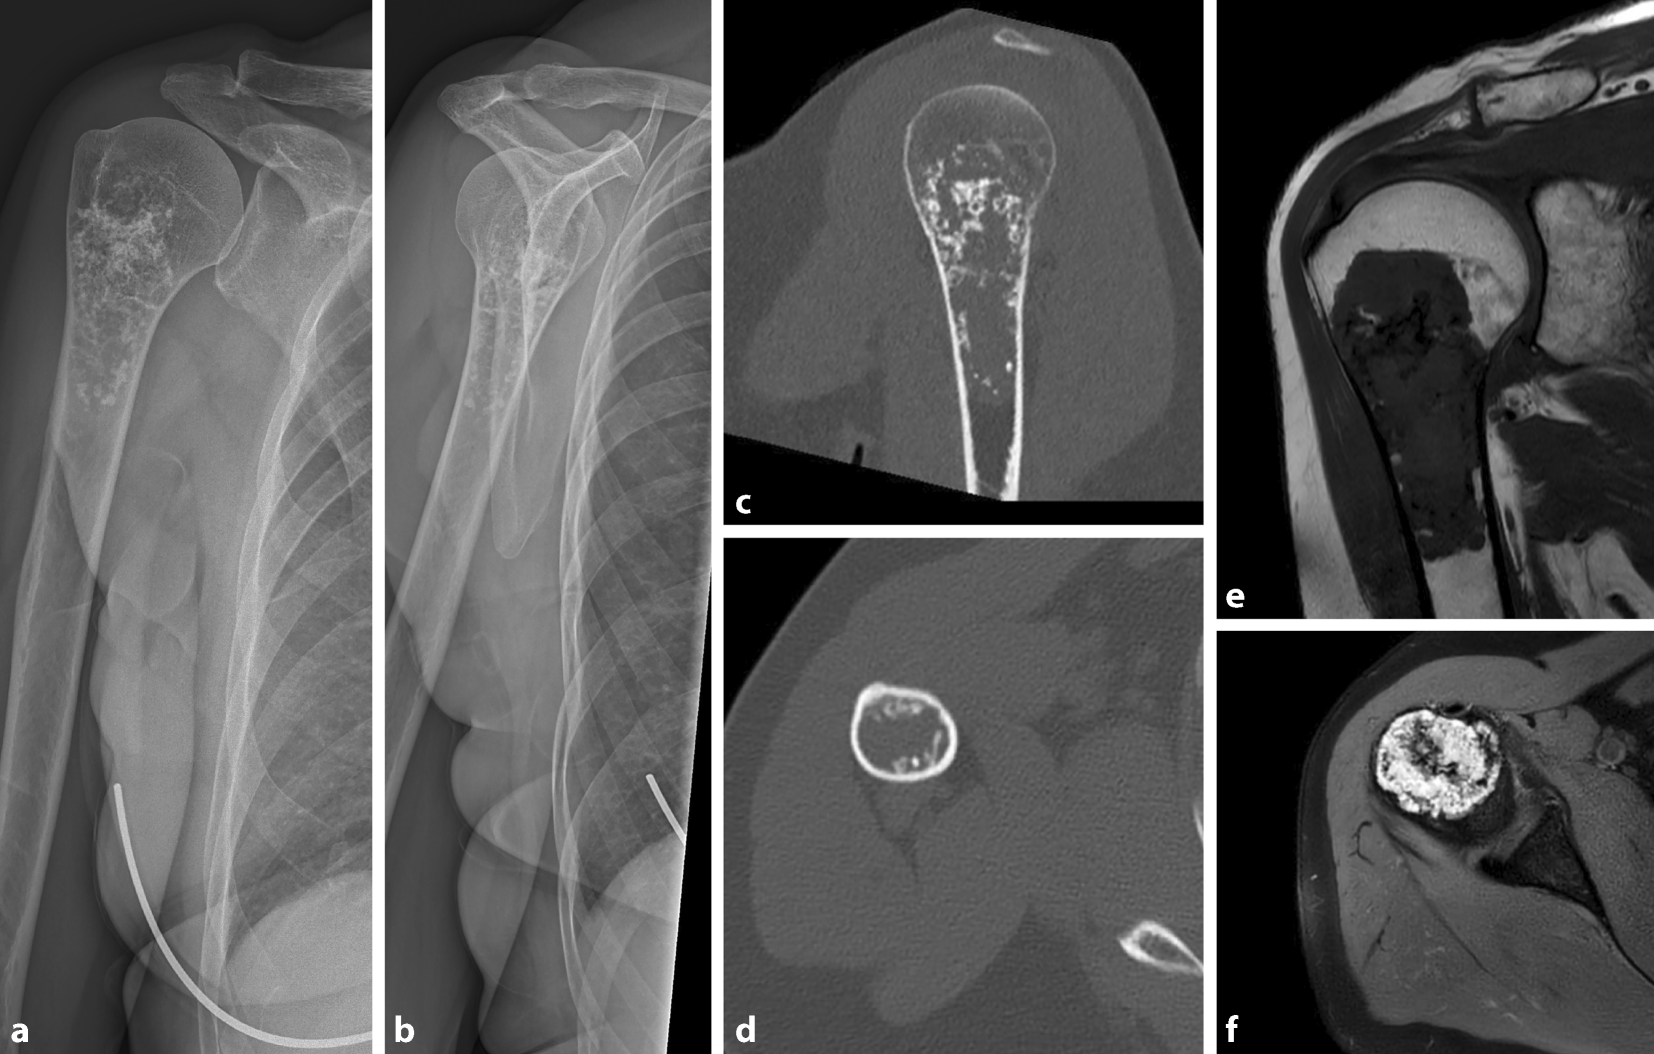

Abb. 1

Röntgenbild des rechten Kniegelenks a. p. (a) und seitlich (b) einer 69-jährigen Patientin, das einen zentral liegenden, popcornartig verkalkten chondrogenen Tumor zeigt. In Zusammenschau mit der MRT (c sagittal, T1 TSE; d koronar, Proton Density [PD] Turbo Spin Echo [TSE] Fett Sat [FS]), die eine zentral im Markraum lokalisierte, gut demarkierte Läsion ohne Scalloping oder umgebendes Knochenmarksödem zeigt, handelt es sich um ein Enchondrom

Bei bildgebendem Verdacht auf das Vorliegen eines chondrogenen Tumors wurde weiterführend eine MRT durchgeführt. In dieser zeigte sich, analog zur Röntgenbildgebung, in der distalen Femurdiaphyse rechts eine in T1 hypointense (Abb. 1c) und in der protonengewichteten, fettunterdrückten Sequenz hyperintense Raumforderung (Abb. 1d) mit zentralen Verkalkungsarealen und einer Größe von 3 cm (kraniokaudal, c.c.) × 2 cm (mediolateral, m.l.) × 2 cm (anteroposterior, a. p.). Es lag kein umgebendes Knochenmarködem und kein endostales Scalloping vor (Abb. 1c, d).

In Zusammenschau von Röntgenbild und MRT wurde die Verdachtsdiagnose eines Enchondroms gestellt

In Zusammenschau von Röntgenbild und MRT wurde die Verdachtsdiagnose eines Enchondroms gestellt. Die Schmerzen wurden auf die Gonarthrose zurückgeführt. Da es bildgebend keinen sicheren Hinweis auf aggressives Verhalten gab (siehe unten), wurde keine ergänzende Kontrastmittel-MRT durchgeführt. Es wurde eine bildgebende Verlaufskontrolle in einem Jahr, erneut mit MRT, empfohlen. Im Fall der Implantation einer Knietotalendoprothese empfehlen wir die Verwendung von patientenspezifischen Schnittblöcken, die keine intramedulläre Ausrichtung benötigen und so einen Kontakt mit dem chondrogenen Tumor vermeiden.